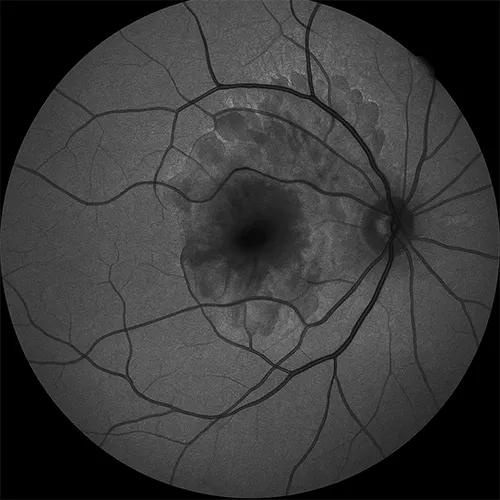

Atrofia geográfica

A atrofia geográfica, forma avançada da degeneração macular relacionada à idade, apresenta áreas bem delimitadas de hipoautofluorescência que correspondem à perda de epitélio pigmentar e fotorreceptores.

A borda ativa pode exibir padrões variados de hiperautofluorescência, sinalizando risco de expansão. O registro seriado permite estimar progressão e avaliar o impacto de terapias, auxiliando na orientação sobre prognóstico e na preservação de hábitos que favoreçam conforto visual.

O exame avalia atrofia geográfica na degeneração macular?

Ícone

Sim. Na atrofia geográfica, a autofluorescência mostra áreas bem delineadas de sinal reduzido que correspondem à perda do epitélio pigmentar e dos fotorreceptores. A borda pode exibir hiperautofluorescência, sugerindo atividade nas margens. O registro seriado permite mensurar expansão, orientar a periodicidade de retorno e alinhar expectativas sobre a manutenção da função visual conforme a evolução documentada ao longo do tempo.